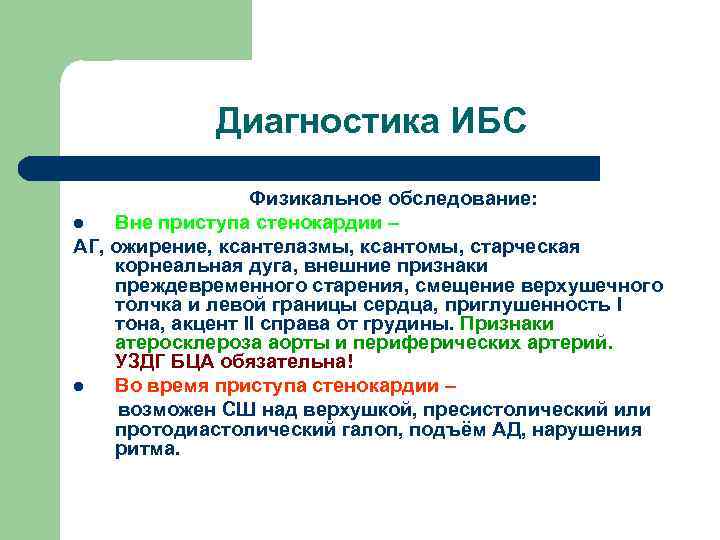

Диагностика ИБС Физикальное обследование: l Вне приступа стенокардии – АГ, ожирение, ксантелазмы, ксантомы, старческая корнеальная дуга, внешние признаки преждевременного старения, смещение верхушечного толчка и левой границы сердца, приглушенность I тона, акцент II справа от грудины. Признаки атеросклероза аорты и периферических артерий. УЗДГ БЦА обязательна! l Во время приступа стенокардии – возможен СШ над верхушкой, пресистолический или протодиастолический галоп, подъём АД, нарушения ритма.